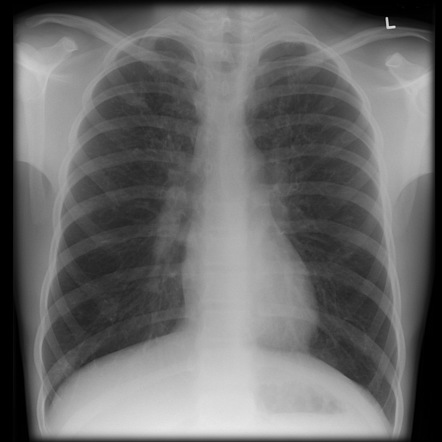

Para confirmar el diagnóstico de pneumonitis, es necesario realizar una evaluación clínica y analizar los síntomas del paciente. Además, se lleva a cabo un examen físico, auscultando los pulmones con un estetoscopio. También se pueden realizar radiografías de tórax, tomografías computarizadas, pruebas de función pulmonar como la espirometría, exámenes de sangre para detección de anticuerpos, y en casos necesarios, una biopsia pulmonar y broncoscopia.

La pneumonitis es una afección pulmonar causada por reacciones alérgicas o inflamatorias a sustancias irritantes. Los síntomas pueden variar, pero es importante estar atento a la tos, la dificultad para respirar, la fiebre y la pérdida de peso inexplicada. El diagnóstico se realiza mediante evaluación clínica, exámenes físicos y pruebas complementarias como radiografías de tórax y estudios de función pulmonar. El tratamiento incluye la reducción de la exposición a los agentes causantes y el uso de medicamentos en casos necesarios. La prevención y los cuidados durante el tratamiento son clave para una recuperación exitosa. En caso de persistencia de los síntomas o recaídas, se debe consultar al médico para ajustar el tratamiento.